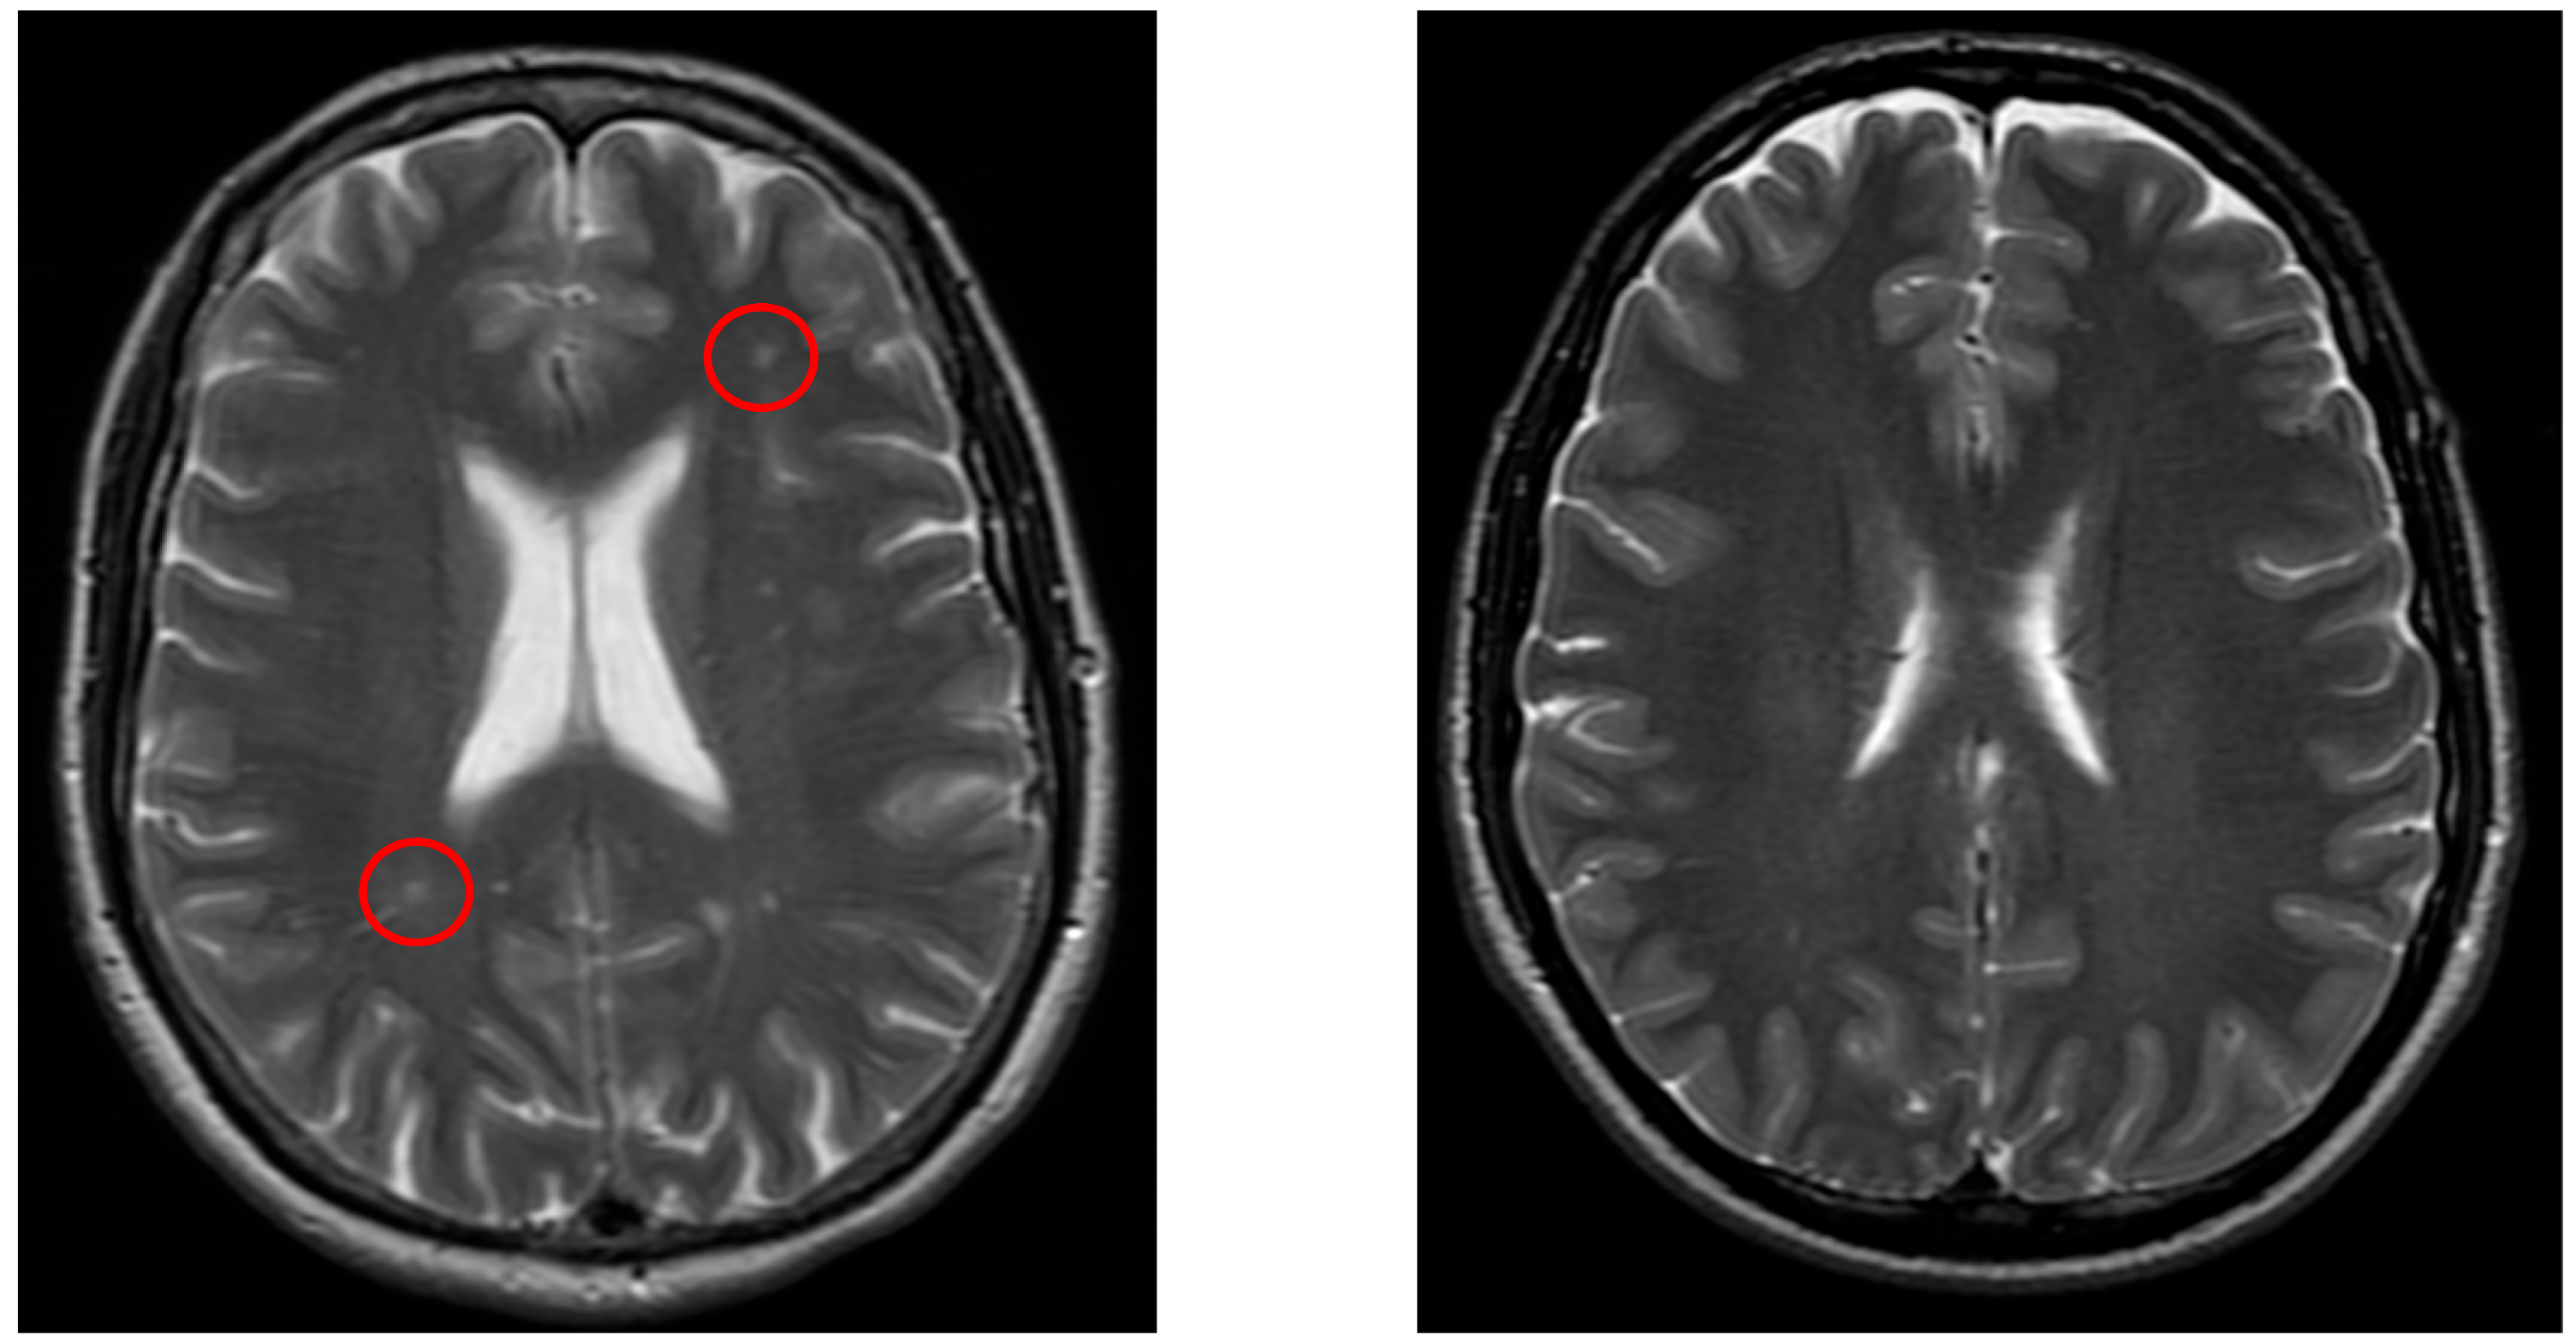

Significant differences were detected in white matter lesions (p = 0.001, see Figure 2), lacunar lesions (p = 0.047), Circle of Willis variation (p = 0.03), and sinusitis/sinus abnormalities (p = 0.005). Other MRI findings, including cortical atrophy, vascular lesion, and vascular encephalopathy, did not show statistically significant differences (p > 0.05).

Figure 3 demonstrates a typical lacunar infarct detected in the vertigo group, in contrast with controls.

Figure 3. The left image (axial T2-weighted) shows lacunar lesions (red circle) in a patient from the vertigo group, whereas the right image (axial T2-weighted) demonstrates a control patient without such lesions.